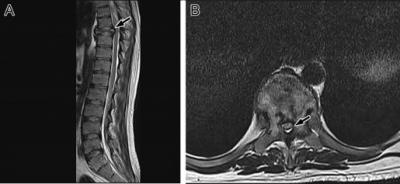

Figure 1: (A) Magnetic resonance imaging (MRI) shows a pathological fracture (arrow) and a lesion in the eighth thoracic vertebral body with loss of the normal marrow fat. (B) MRI shows a heterogeneous lesion involving the body and both pedicles of the eighth thoracic vertebra with narrowed spinal cord canal (arrow).